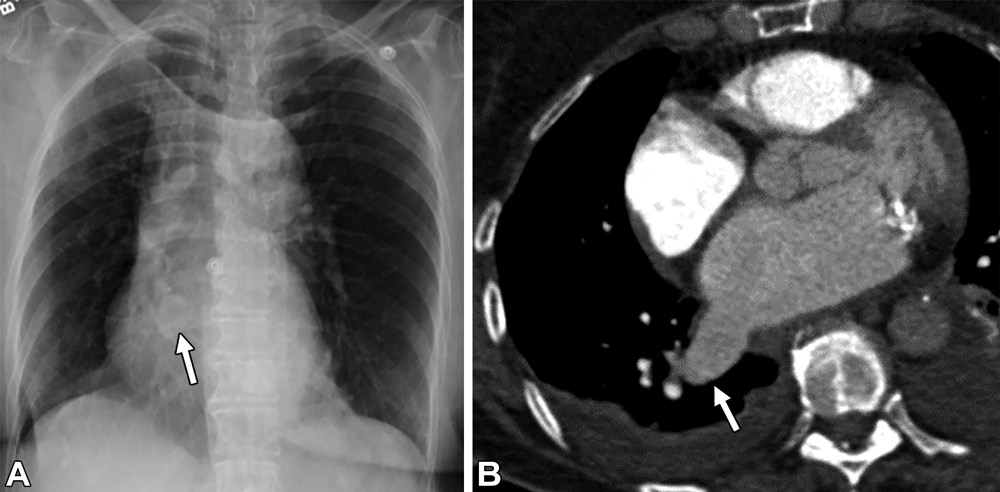

肺静脉曲张。54岁男性,胸片异常。(A)前后位胸片可见右肺下叶异常扩张的血管结构(白色箭头)。(B)轴位CT增强图,可见右肺下叶肺静脉曲张。